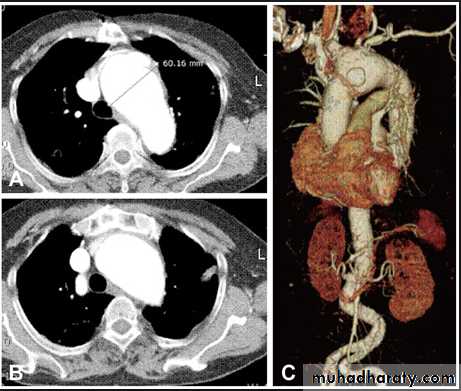

Hodgkin Lymphoma. A. Posteroanterior chest radiograph in a 35-year-old man shows a large, lobulated mediastinal mass. B. Contrast-enhanced CT at the level of the aortic arch shows bulky anterior and middle mediastinal lymphadenopathy